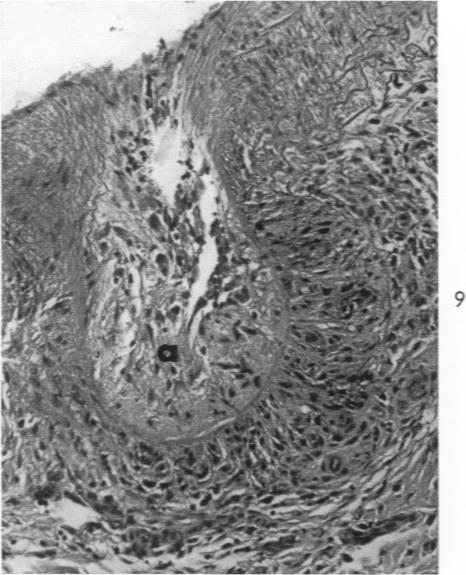

Hypertension of the pulmonary circulation due to congenital glomoid obstruction of the pulmonary arteries.

Am J Pathol. 1961 Jul;39(1):75-93.